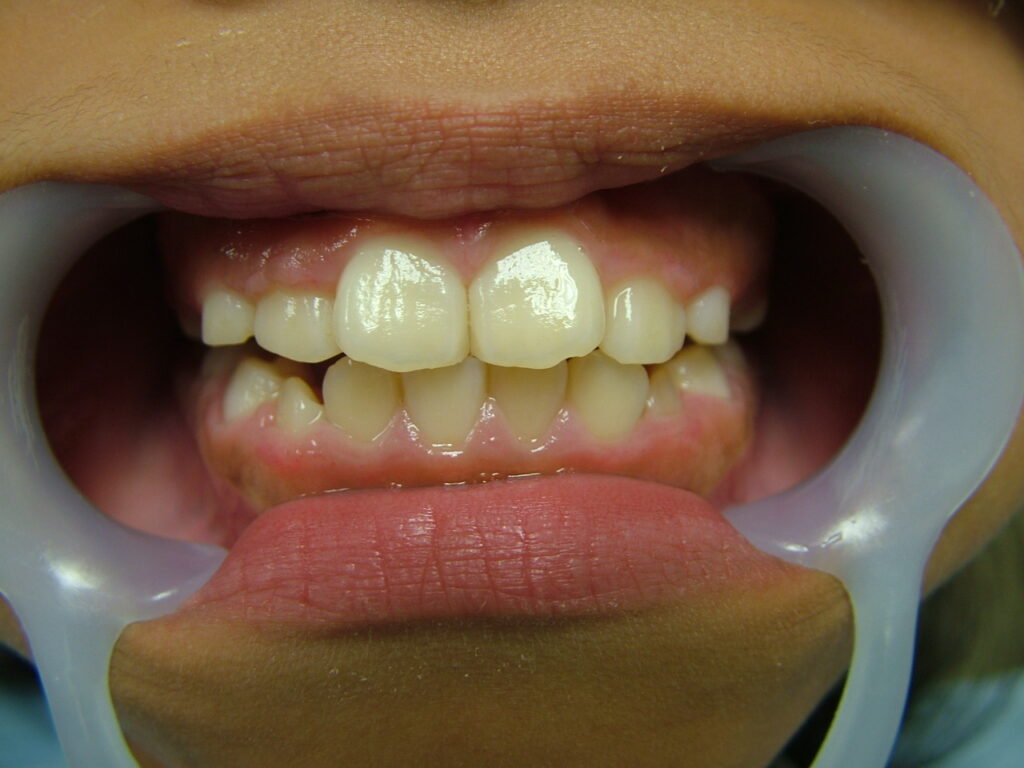

治療後

治療後のコメント

虫歯や歯肉炎の発症なく、まずまずの状態で1期治療を終了したと思います。もう少し上下顎拡大も考えましたが口が大きくなることを考慮して、最小限のディスキングで対応しました。親御さん、子供さん共に非抜歯での矯正を希望されましたが、今後シャープな口元を希望される場合、矯正の専門医で小臼歯4本抜歯ワイヤー矯正されるのも良いかもしれません。しかし舌房が狭くなり、噛みしめが誘発された方(歯周病の悪化、肩こり、知覚過敏、不定愁訴等)を数多く見てきているため、私は成人抜歯矯正(2期治療)をやるつもりはありません。(注、私は全ての抜歯矯正を否定しているわけではありません。正しく舌房の確保、舌のポジション、上下7番のコントロールを考えた矯正医が行うのは素晴らしいと思っています。)